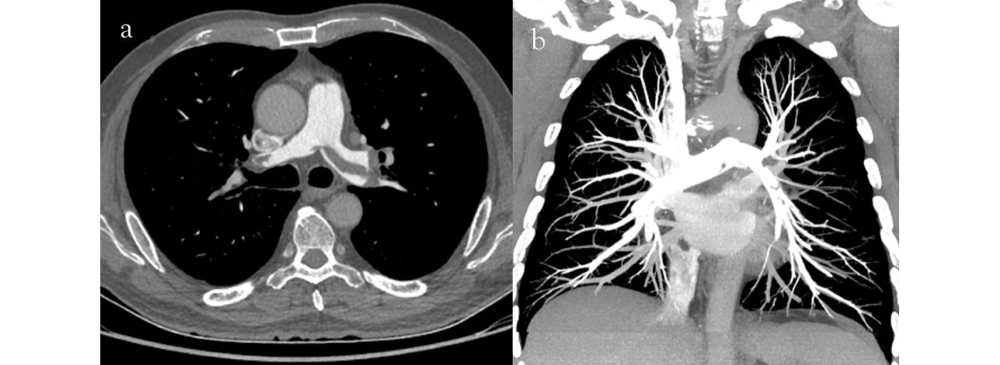

CT Pulmonary Angiogram (CTPA) in Pallavaram

A CT Pulmonary Angiogram (CTPA) is the gold standard for detecting pulmonary embolism (PE) — a serious condition caused by blood clots in the lungs. This scan provides a clear view of the pulmonary arteries, helping doctors confirm the diagnosis quickly and start life‑saving treatments without delay.

At our centre, the procedure is performed using advanced CT technology and safe contrast agents to deliver sharp, accurate images. Patients experiencing symptoms like sudden chest pain, shortness of breath, or unexplained rapid heartbeat may be referred for CTPA. Our experienced radiologists interpret the scans with precision, ensuring your doctor has the information needed to act promptly.

• Provides detailed images of pulmonary arteries